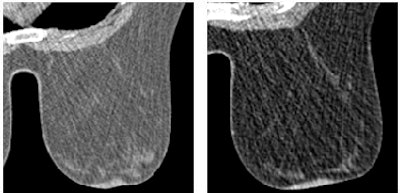

![]()  |

| Fifty-two-year-old woman with invasive ductal carcinoma in left breast. (A and B) Dynamic MDCT images at baseline (A) and one minute (B) after contrast administration depict an irregular lesion with homogeneous enhancement; evaluation of time-attenuation curve showed washout pattern. (C and D) Coronal and sagittal multiplanar reconstructions one minute after contrast administration show lesion in A and B located in upper left quadrant of breast, approximately 2 cm behind nipple. |